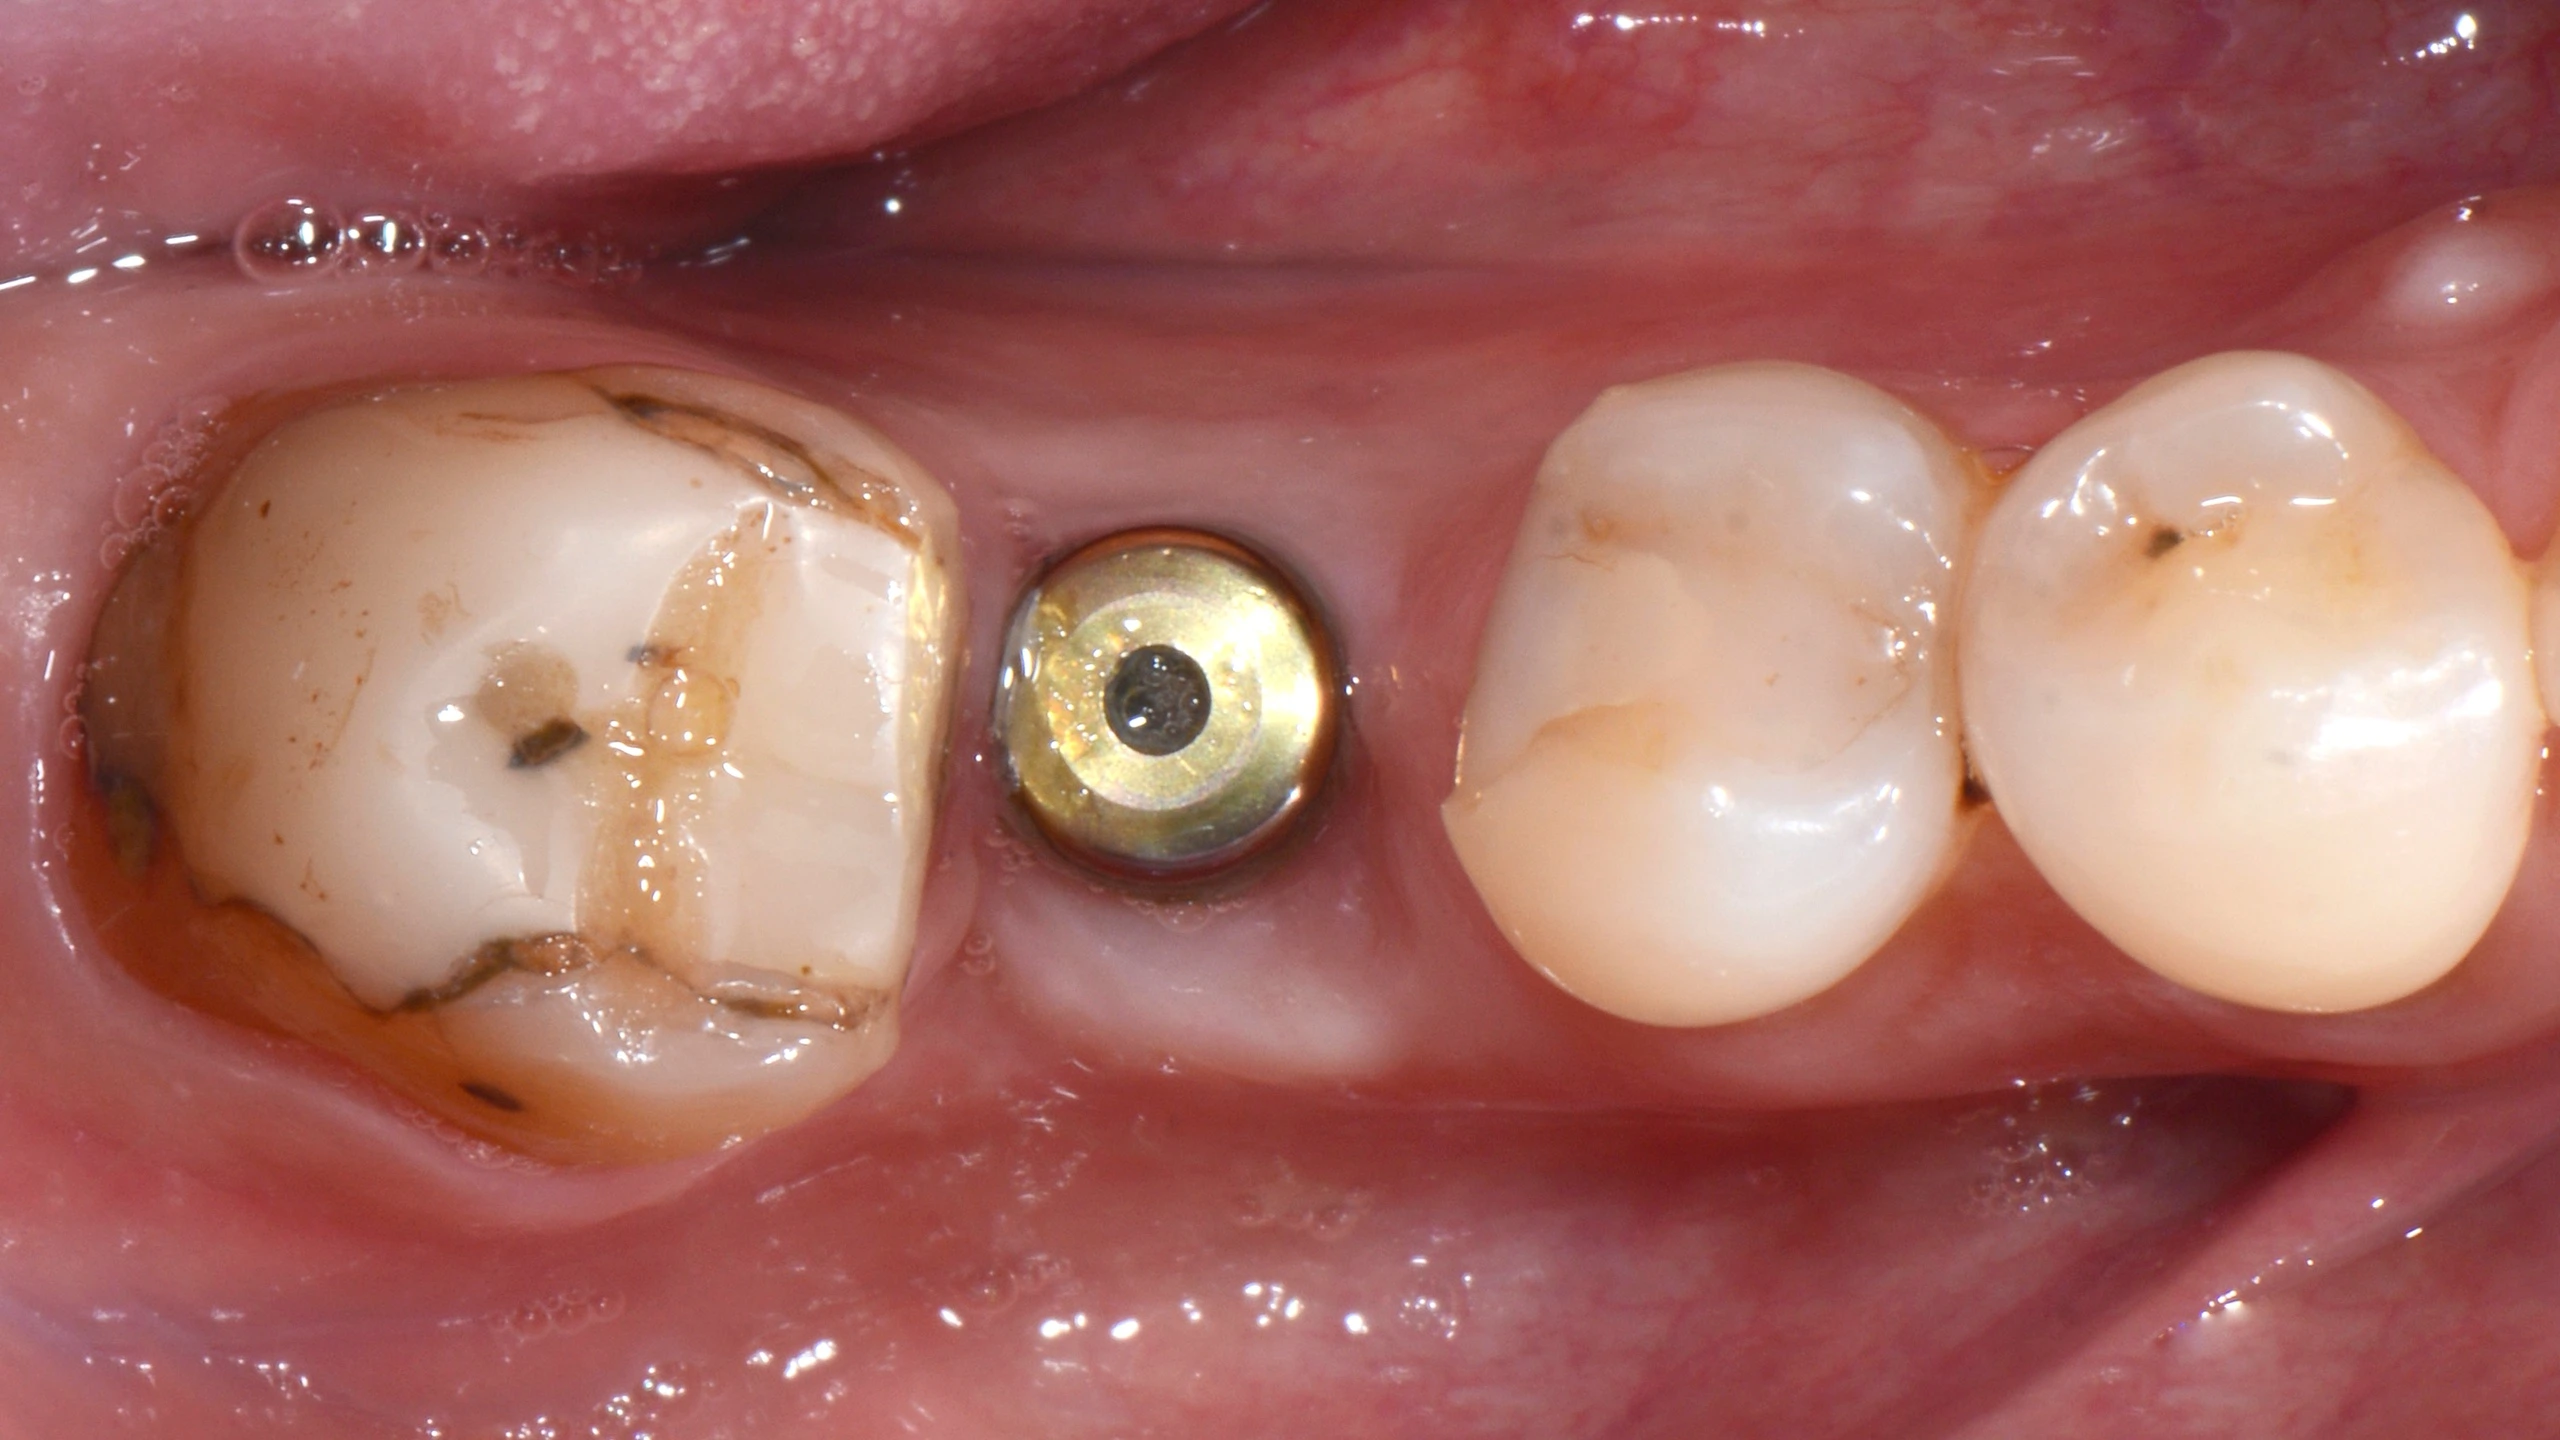

В данном кейсе не стали прибегать к ортодонтическому лечению, а просто установили имплантат MIS С1

Далее провизорное протезирование с препарированием зуба 47, и после формирования профиля постоянное протеизрование коронками на цементной фиксации на имплантате и на зубе. Зачастую, не всегда вижу необходимость в апрайте семерок, особенно, если в дальнейшем их еще и требуется покрыть коронкой.